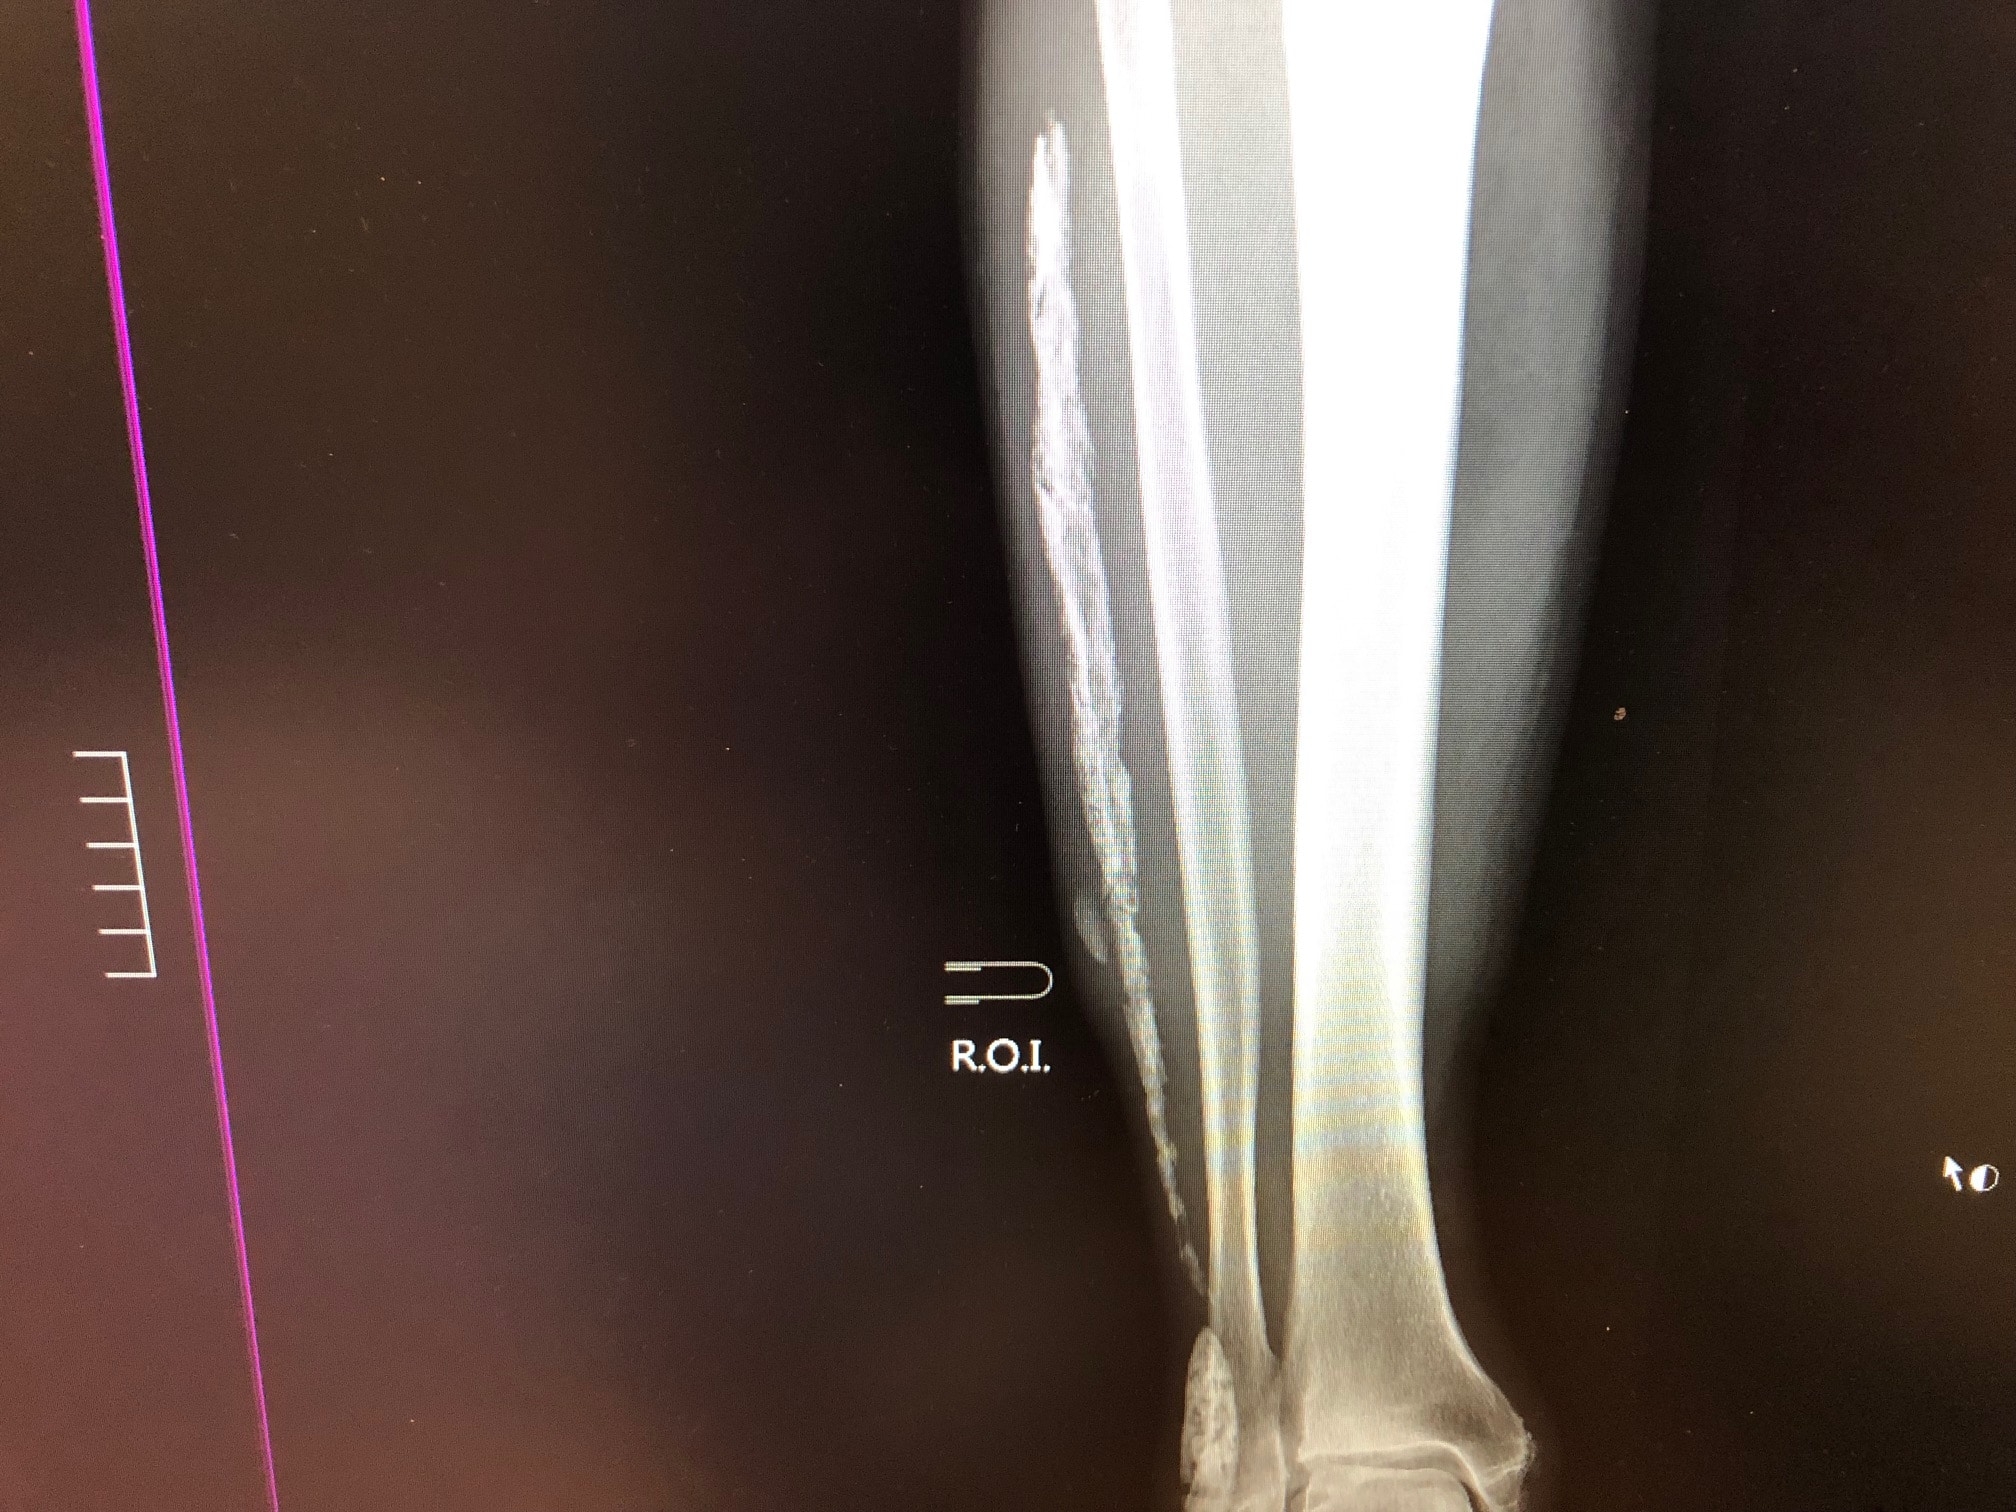

• Assessment and management of acute orthopaedic injuries including sport and work-related injuries

• Referral for scans or review by a specialist